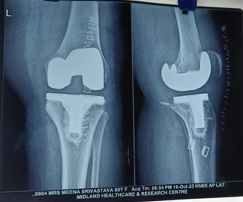

Knee Replacement Surgery, also known as knee arthroplasty, is a surgical procedure that aims to relieve pain and restore function in severely damaged knee joints. It involves replacing the damaged joint surfaces with artificial implants made of metal and plastic.